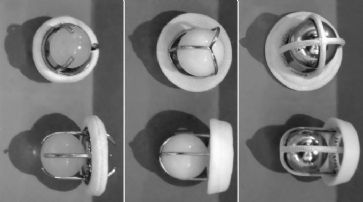

Das Team um Michael McAlpine kombinierte Verfahren der 3D-Bildgebung und des 3D-Drucks, um eine Richtschnur für eine Nervenbahn aus Silikon herzustellen, die - mit biochemischen Informationen versehen - komplexe Nerven wiederherstellt.

Das Nachwachsen von gerade verlaufenden Nerven ist in der Vergangenheit bereits gelungen. Die in «Advanced Functional Materials» veröffentlichten Ergebnisse beschreiben jedoch erstmals die Möglichkeit der Herstellung eines verzweigten Nervs wie des Ischiasnervs. Die Funktionsfähigkeit der Nervenbahn wurde im Labor an Ratten getestet.

In einem ersten Schritt wurde mit einem 3D-Scanner die Struktur des Ischiasnervs einer Ratte nachgebildet. Mit einem speziellen 3D-Drucker wurde dann eine Anweisung für die zu regenerierende Nervenbahn zur Regeneration hergestellt. Anschliessend wurde der neue Nerv an den zuvor gekappten Enden implantiert.

Innerhalb von zehn bis zwölf Wochen verbesserte sich die Gehfähigkeit des Tieres.